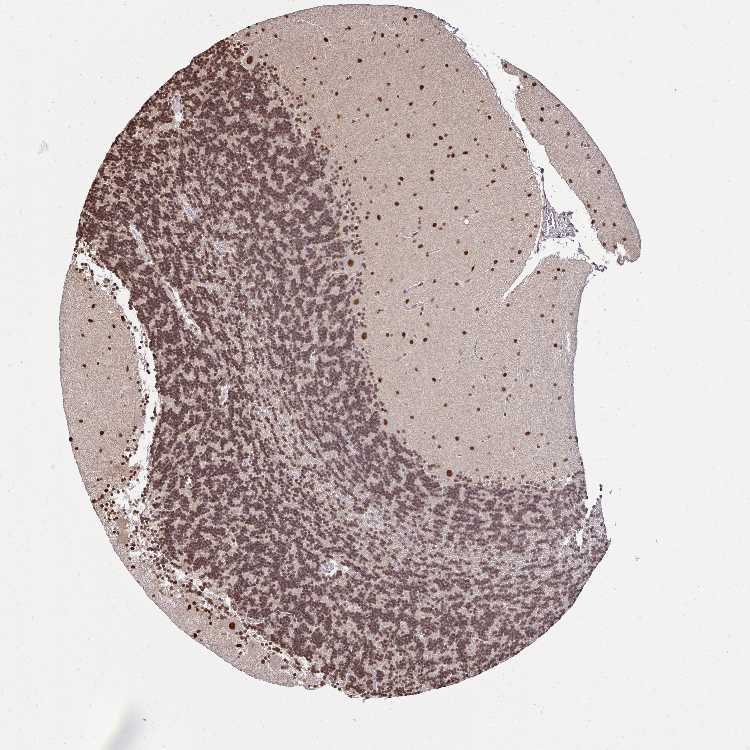

BRAIN CEREBELLUM Show tissue menu

CEREBELLUM - Expression summary

CEREBELLUM - Antibody stainingi

Antibody staining in the annotated cell types in the current human tissue is reported as not detected, low, medium, or high, based on conventional immunohistochemistry profiling in selected tissues. This score is based on the combination of the staining intensity and fraction of stained cells.

Each image is clickable and will lead to virtual microscopy that enables deeper exploration of all samples and also displays staining intensity scores, fraction scores and subcellular localization as well as patient and tissue information for each sample.

Antibody HPA054823

Purkinje cells High

Cells in granular layer Medium

Cells in molecular layer High